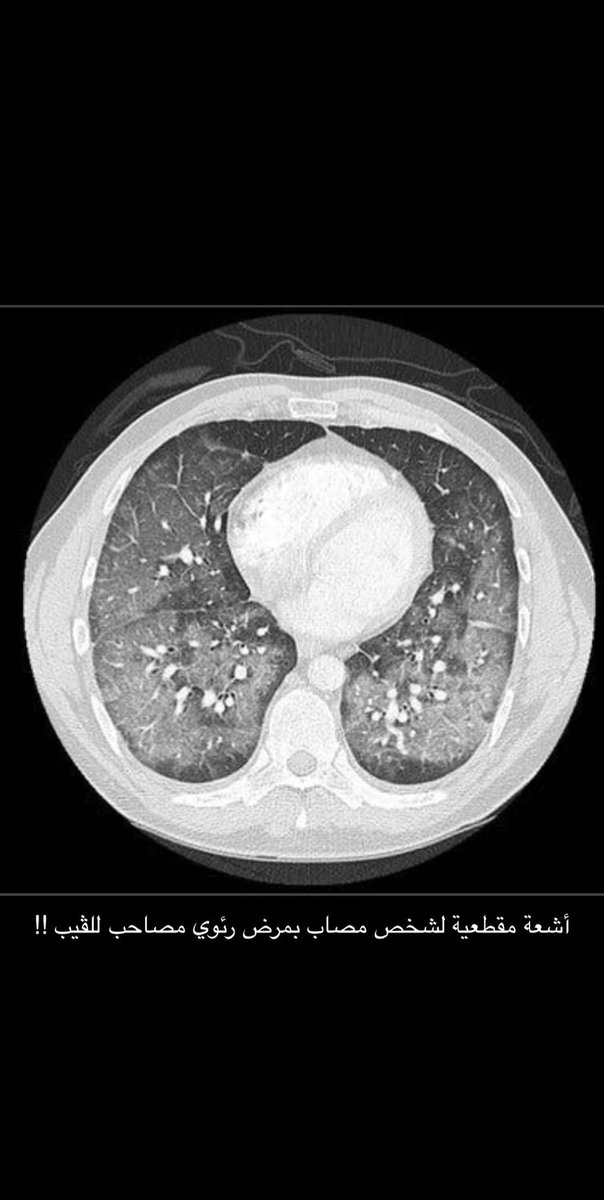

في هذا الثريد ان شاء الله ، بتكلم فيه عن الشيشة الإلكترونية أو الڤيب و بعض الدراسات الحديثة و الخطيرة عنه !!